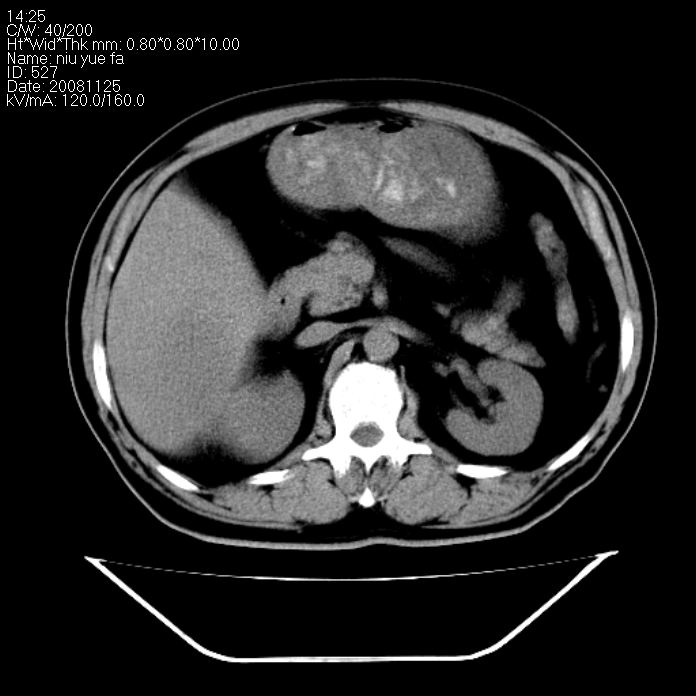

巨块型肝癌,坏死,出血;胆囊结石

1)考虑肝右叶巨块型肝癌并坏死、出血;建议行ct增强扫描检查进一步明确诊断。2)胆囊结石,胆囊炎。

考虑肝右叶巨块型肝癌并坏死、出血;建议行ct增强扫描。胆囊结石。

肝右叶巨块型肝癌并坏死、出血;胆囊结石,胆囊炎。